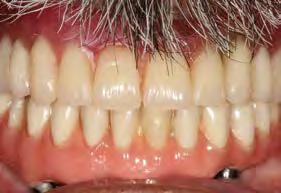

Se presenta una paciente de 17 años y 5 meses diagnosticada con clase I esquelética, hipodivergente, clase I molar y canina izquierda, clase II molar derecha y la clase canina derecha sin identificar debido al canino 13 retenido, mordida abierta en sector de laterales, overjet y overbite disminuidos, línea media dental superior desviada a la derecha y la inferior desviada a la izquierda, microdoncia de los incisivos 12 y 22. Objetivo: mantener el perfil facial, y las relaciones esqueléticas maxilomandibulares, realizar cirugía del 13, corrección de rotaciones dentales en el maxilar, mantener la clase I molar izquierda y obtener la clase I molar derecha, mantener la clase I canina izquierda, obtener clase I canina derecha, cerrar mordida abierta de sector de laterales, corrección del overjet y overbite, corrección de líneas medias dentales, manejo de Bolton, mejorar estado periodontal, lograr correcta intercuspidación, guía de desoclusión canina e incisiva y restauración de los dientes 12 y 22. Tratamiento: alineación, nivelación, tracción canina del 13, detallado y retención. Tiempo de tratamiento: 2 años y 9 meses.

Caso clínico

Se presenta una paciente de 13 años 5 meses con el motivo de consulta “es que no me baja el colmillo”. En los estudios extraorales se ve el perfil concavo y labios en contacto durante el reposo (Figura 1). En los estudios intraorales tenemos , clase I esquelética, con crecimiento hipodivergente (Figura 2), clase II molar derecha y clase I molar y canina izquierda, la clase canina derecha no determinada

Figura 1. Perfil, frente en reposo, sonrisa.

(ND), órgano dental (OD) 13 retenido, mordida abierta en sectores laterales, overjet de 3 mm y overbite de 10%, líneas medias dentales desviadas y microdoncia de OD 12 y 22.

Resultados

El tiempo de tratamiento fue de 2 años y 9 meses se lograron los objetivos del tratamiento manteniendo el perfil facial, y las relaciones esqueléticas maxilomandibulares. Se realizó la tracción del 13, la corrección de rotaciones dentales en el maxilar, se mantuvo la clase I molar izquierda y se obtuvo la clase I molar derecha. La clase I canina izquierda, y se logró la clase I canina derecha, cerrar mordida abierta de sectores laterales, corrección del overjet y overbite, corrección de líneas medias dentales, manejo de Bolton de arcada superior, mejorar estado periodontal, lograr correcta intercuspidación, guía de desoclusión canina y guía incisiva y la restauración de los dientes 12 y 22

(Figura 5). Una vez terminado el tratamiento, la estabilidad a largo plazo mediante la retención con un circunferencial con finger en los incisivos 12 y 22 para la arcada superior y retenedor termoformado para la arcada inferior.

Radiografía panorámica final el canino 13 es incorporado al arco (Figura 5) y los terceros molares en etapa de formación.

Estudios intraorales finales en las fotografías oclusales, se ven los laterales 12 y 22, así como la incorporación del canino al arco con torque adecuado (Figura 6). En la lateral derecha e izquierda la restauración estética de los laterales superiores,

sin rotaciones ni discrepancia de Bolton.